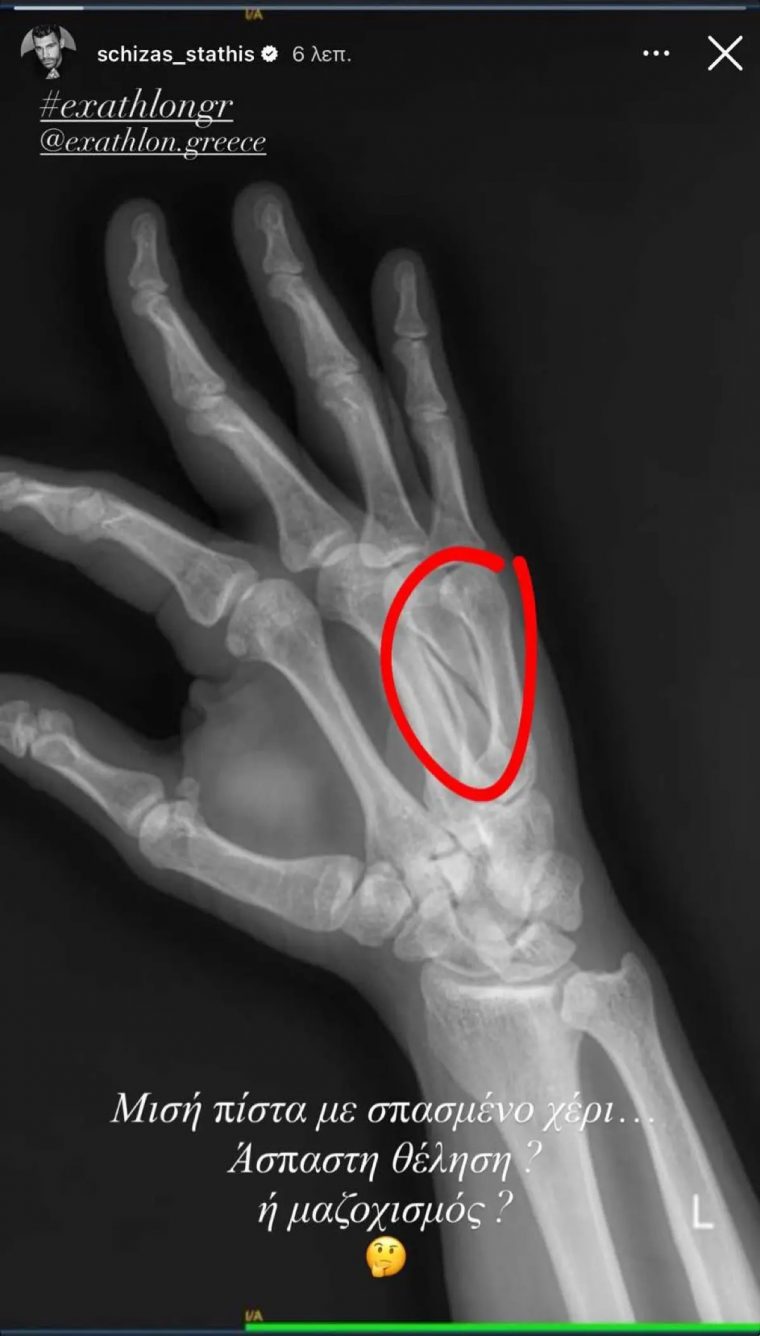

Στάθης Σχίζας - Exathlon: Μας δείχνει την ακτινογραφία του μετά το κάταγμά στο χέρι – «Μαζοχισμός;»

Κατά τη διάρκεια αγωνίσματος με αντίπαλο τον Άρη Σοϊλέδη, χτύπησε δυνατά το χέρι του και οι εξετάσεις έδειξαν κάταγμα, γεγονός που τον κρατά και πάλι εκτός.

Μετά την προβολή του επεισοδίου, ο ίδιος ανέβασε στο Instagram μια φωτογραφία από την ακτινογραφία του, γράφοντας χαρακτηριστικά:

«Μισή πίστα με σπασμένο χέρι… Άσπαστη θέληση ή μαζοχισμός;»